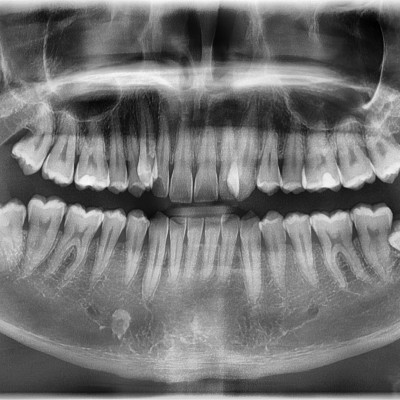

#28,38 사랑니 발치 #28,38 사랑니 발치 구강 외과 전문의가 당일 발치하였습니다. -------------------------..

작성자 이턱이 작성일 01-29 조회 5